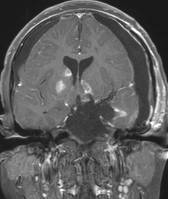

病例1:患儿男性,9岁。因反复出现意识丧失、视力下降半年收入院。入院后CT及 MRI显示颅内有形态不规则、“超大型”的颅咽管瘤,最大径约10厘米,见图1、图2。

图2.术前MRI

白色箭头指示肿瘤下极达枕大孔区